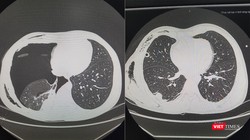

Qua thăm khám và làm các xét nghiệm, các bác sĩ Bệnh viện Đà Nẵng phát hiện bệnh nhân bị Brugada type 1. Với tiên liệu bệnh lý hiếm gặp nhưng cực kì nguy hiểm, có thể dẫn đến loạn nhịp thất, rung thất trên điện tâm đồ ECG, gây ngất xỉu và làm gia tăng nguy cơ đột tử do tim.